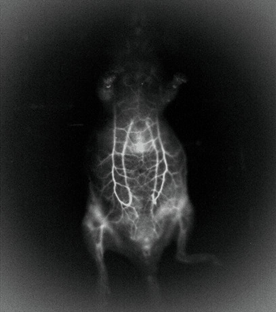

图1-近红外二区宏观活体成像示意图

如上图所示,在小鼠体内注射近红外二区荧光染料,选择适配的光学成像镜头。虽然近红外二区发射的波长较长,能避免组织自发荧光和光子散射等背景干扰,使得穿透的深度更深,但是发射出的荧光还是处于弱光等级,需要利用深度制冷短波红外相机进行成像探测。图2所拍摄照片是采用我司GS-SW6401725-80-U相机进行拍摄。